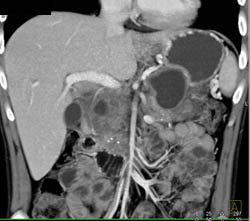

Encased SMA and Celiac Arteries Due to Pancreatic Cancer